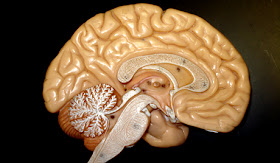

Dois cientistas israelenses desenvolveram um capacete que emite ondas magnéticas para o cérebro e que, segundo pesquisas, tem efeitos significativos no combate a transtornos como a depressão e o vício do fumo.

O capacete, desenvolvido pelo neurocientista Abraham Zangen e pelo físico Yiftach Roth, emite ondas magnéticas em alta frequência para regiões mais profundas no cérebro, que até hoje podiam ser acessadas só com intervenções cirúrgicas ou choques elétricos. Por intermédio dos estímulos, eles obtiveram resultados positivos tanto em casos de pacientes que sofrem de depressão profunda como em pessoas que já tinham tentado parar de fumar por outros meios e não conseguiram.

Entretanto, de acordo com Roth, o sistema, denominado Estimulação Transcraniana Magnética Profunda (Deep TMS, em inglês) pode ser eficaz no tratamento de um leque "muito amplo" de problemas, como o mal de Parkinson, distúrbio bipolar, mal de Alzheimer, autismo, distúrbio obsessivo-compulsivo, dependência de drogas e alcoolismo.